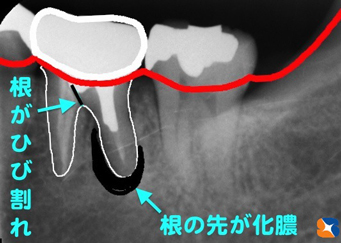

奥歯には根が2本ある

コラム「奥歯には根が2本ある」の画像